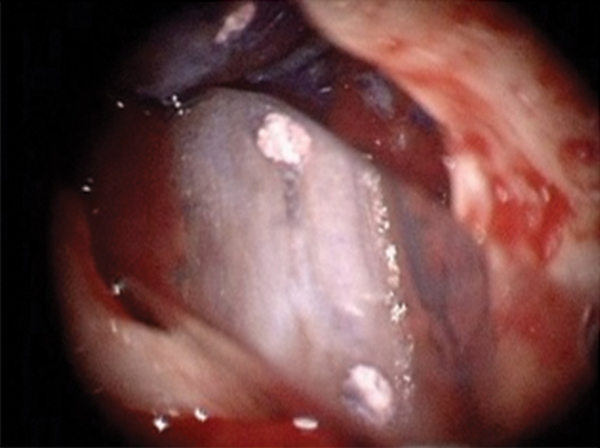

Fig 16. Post apicoectomy. Courtesy of Dr. Sam Kratchman.

Figure 16